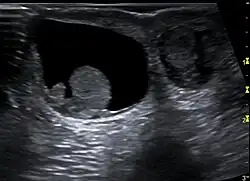

Neben der körperlichen Untersuchung mit Inspektion und Palpation ist eine zuverlässige Abgrenzung von Hodentumoren, Blutergüssen und Elephantiasis vor allem mittels Ultraschall möglich.[6] Die Hydrozele zeigt sich in einer meist schmerzlosen Volumenzunahme des Hodensacks ohne Anzeichen einer Entzündung. Bei stärkerer Volumenzunahme kann Druck- oder Schweregefühl auftreten. In der Sonografie zeigt sie sich als echoferier Raum, bei entzündlich bedingten Hydrozelen können scheidewandähnliche Fibrinstränge auftreten. Bei einer geringen Flüssigkeitsmenge („schlaffe Hydrozele“) ist der Hoden frei beweglich, bei einer stärkeren („straffe Hydrozele“) liegt er randständig. Die Durchblutung ist nicht beeinträchtigt. Bei längerem Bestehen kann es zu einer Schrumpfung (Atrophie) des Hodens kommen.[7]